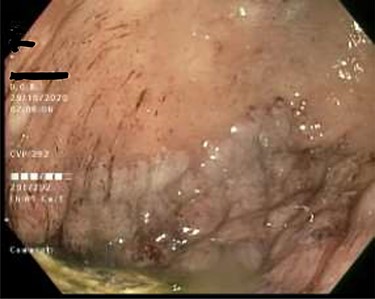

As work up for his abdominal pain and anemia he underwent gastroscopy on 29 October 2020 that revealed congested and nodular gastric mucosa (mass-like) and at lesser extend in the first and second part of duodenum (Figs 1 and 2). Biopsies were taken from the gastric lesion and duodenum. Histopathological findings from gastric mass and duodenum showed marked stromal hyalinosis, which appeared as a cellular pink material on H&E stain (Figs 3 and 5). Congo red stain (amyloid stain) showed apple green birefringence under polarized light on both gastric and duodenal biopsies (Figs 4 and 6).

Duodenal mucosa seen by endoscopy shows some erythema and nodularity.